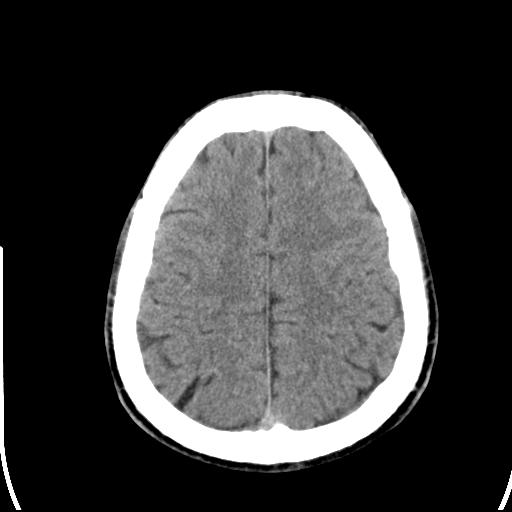

标题: CT25435:头皮下高密度影???

头皮下高密度结节影???临床上在老年男性比较常见。大家看看是什么?成因是? 本例患者,男性,51岁。外伤来诊。无染发史及发根植入史。